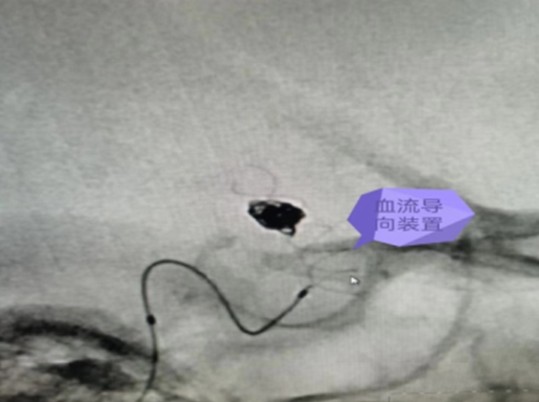

衡陽市中心醫(yī)院神經(jīng)外科主任李遠志緊急組織醫(yī)師團隊開展術(shù)前討論,分析認為結(jié)合該動脈瘤的形態(tài)及部位等特點,診斷為右側(cè)后交通段血泡樣動脈瘤,再次破裂風險極高,建議積極手術(shù)治療。手術(shù)開顱夾閉手術(shù)風險高,難度大,而常規(guī)支架輔助+彈簧圈栓塞后期動脈瘤進展及復發(fā)可能性高。較好的治理方式為血流導向裝置置入+彈簧圈栓塞治療,并取得家屬同意。

7月14日,在麻醉科及介入手術(shù)室的密切配合下,神經(jīng)外科醫(yī)師團隊順利完成了此例后交通段血泡樣動脈瘤血流導向裝置+彈簧圈栓塞手術(shù),拆除了龍女士腦子里的“不定時炸彈”。

據(jù)悉,顱內(nèi)血流裝置(PED)是一種治療顱內(nèi)復雜動脈瘤新型的治療方式,通過置入所到病變動脈后,使動脈內(nèi)的血流動力學發(fā)生改變,緩慢的在動脈瘤內(nèi)形成血栓,內(nèi)膜上皮攀爬到支架表面從而來修復病變血管使其發(fā)生血管重建來修復病變的載瘤動脈。血流導向裝置的發(fā)展更新了動脈瘤的治療理念,對顱內(nèi)復雜動脈瘤的治療結(jié)果產(chǎn)生革命性的變化,具有手術(shù)微創(chuàng),操作簡單,安全性相對較高,在降低動脈瘤復發(fā)方面更具有優(yōu)勢。